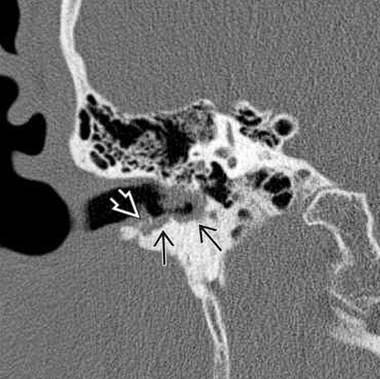

El colesteatoma del conducto auditivo externo se observa en la Tomografía computarizada simple de oído como una lesión con densidad a tejidos blandos en el CAE con erosión ósea asociada y fragmentos óseos intralesionales (Figura 6). La erosión ósea adyacente a la lesión de tejido blando puede ser lisa, similar a un colesteatoma del oído medio; sin embargo, la erosión puede ser irregular debido al hueso necrótico y la periostitis. Por lo general, las paredes inferior y/o posterior están involucradas. Es importante evaluar la extensión hacia la cavidad del oído medio y la integridad del canal del nervio facial, tegmen timpánico y celdillas mastoideas, ya que estas características pueden cambiar el manejo quirúrgico. Es importante destacar que, aunque la resonancia magnética es ampliamente utilizada en la evaluación de enfermedades del oído interno y medio, su utilidad en el diagnóstico de colesteatoma del conducto auditivo externo es limitada. La secuencia de difusión puede llegar a ser de utilidad para la realización de diagnósticos diferenciales con otras lesiones del CAE.

(Figura 6). Corte coronal. Muestra un CCAE como una lesión submucosa erosiva y dentada en el CAE óseo inferior.

Se observa erosión ósea con fragmentos óseos dentro de la matriz del colesteatoma.